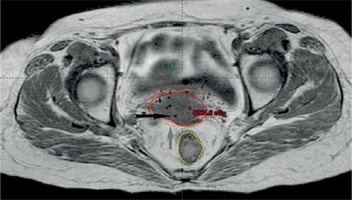

Gross tumor volume, high-risk clinical target volume (HR-CTV), intermediate-risk clinical target volume (IR-CTV), and OARs were delineated with the use of MR T2 weighted images, following GEC-ESTRO guidelines. HR-CTV delineation was challenging, as pre-brachy MR images were not available. This was overcome by changing the contrast resolution and EUA findings (Figure 1). T1 weighted images were helpful for a catheter reconstruction, and the catheters were better appreciated as black straight lines without any interruptions. Haack et al. showed that plastic catheters are well suited for MR-based reconstruction in T1 images and all catheters were visible without artifacts [9]. Depending of the extent of disease, the active lengths of the implant ranged from 6-8 cm. The dose prescribed was 20 Gy in 4 fractions (30 Gy low-dose-rate [LDR] equivalent [EQD2]) to HR-CTV, 6 hours apart, and delivered over two days. Doses of 2 cc of bladder and rectum were restricted to less than 4.0 and 3.7 Gy per fraction, respectively. With our initial experience, the dose escalation was considered to be 6 Gy per fraction. Treatment plans were performed using volumetric optimization with 5 mm dwell position (Figure 2). The OARs constraints were met using manual dragging of isodose lines. The treatment was executed using 192Ir Gammamed Plus HDR remote afterloading machine (Varian Medical Systems, Palo Alto, CA, USA), with 192Ir high activity of 10 Ci max, source of 4.6 mm active length and 0.9 mm in diameter.